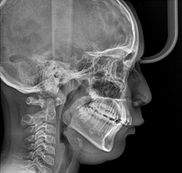

The treatment plan was discussed and it was decided to use the 9mm Hyrax type expansion screw, bands were made in the first molars, which were not cemented to be removed with an impression and to obtain a working model, in which this screw was adapted (Figure 2&3). The labial frenectomy was performed by the specialty of Periodontics using the classic rhomboidal technique, then on October 23rd, 2023 the cementation of the 9mm. hyrax type disjunctor was performed, applying two daily activations until the formation of the diastema (Figure 4). Applying two daily activations until the formation of the diastema (Figure 4). The appliance was activated ¼ turn in the morning and ¼ turn at night (0.5/day) for a total of 18 activations. Maxillary expansion was chosen instead of premolar extractions due to oral respiration. He is a patient with a restricted airway, therefore extractions would accentuate this condition; on the contrary, expanding the airway would be advantageous for his breathing, on the other hand, by providing the necessary space for the correct location of the tongue, it favors the stability of the upper arch.6 At all times, both the patient and the mother were told in detail how the hyrax-type circuit breaker works and that they could feel slight discomfort, as well as pain and tingling sensations. After 18 days, separation of the median suture was observed. Then, acrylic was added to the screw with the disjunctor to be used as a containment appliance for 3 months to allow time for the bone neoformation of the suture, while the 0.018 royh brackets were placed to align her teeth (Figure 5).

Figure 2.

Figure 3.

Figure 4.

Figure 5 Comparative radiographic analysis.